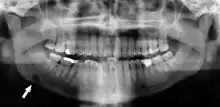

Stafne's defect is usually discovered by chance during routine dental radiography.[11] Radiographically, it is a well-circumscribed, monolocular, round, radiolucent defect, 1–3 cm in size, usually between the inferior alveolar nerve (IAN) and the inferior border of the posterior mandible between the molars and the angle of the jaw. It is one of the few radiolucent lesions that can occur below the IAN. The border is well corticated and it will have no effect on the surrounding structures. Computed tomography (CT) will show a shallow defect through the medial cortex of the mandible with a corticated rim and no soft tissue abnormalities, with the exception of a portion of the submandibular gland. Neoplasms, such as metastatic squamous cell carcinoma to the submandibular lymph nodes or a salivary gland tumour, could create a similar appearance but rarely have such well defined borders and can usually be palpated in the floor of the mouth or submandibular triangle of the neck as a hard mass. CT and clinical exam is typically sufficient to distinguish between this and a Stafne defect. The Stafne defect also tends to not increase in size or change in radiographic appearance over time (hence the term "static bone cyst"), and this can be used to help confirm the diagnosis.[11] Tissue biopsy is not usually indicated, but if carried out, the histopathologic appearance is usually normal salivary gland tissue. Sometimes attempted biopsy of Stafne defects reveals an empty cavity (possibly because the gland was displaced at the time of biopsy), or other contents such as blood vessels, fat, lymphoid or connective tissues. Defects of the anterior lingual mandible may require biopsy for correct diagnosis at this unusual location.[5] The radiolucent defect here may be superimposed on the lower anterior teeth and be mistaken for an odontogenic lesion. Sometimes the defect may interrupt the contour of the lower border of the mandible, and may be palpable. Sialography may be sometimes used to help demonstrate the salivary gland tissue within the bone.